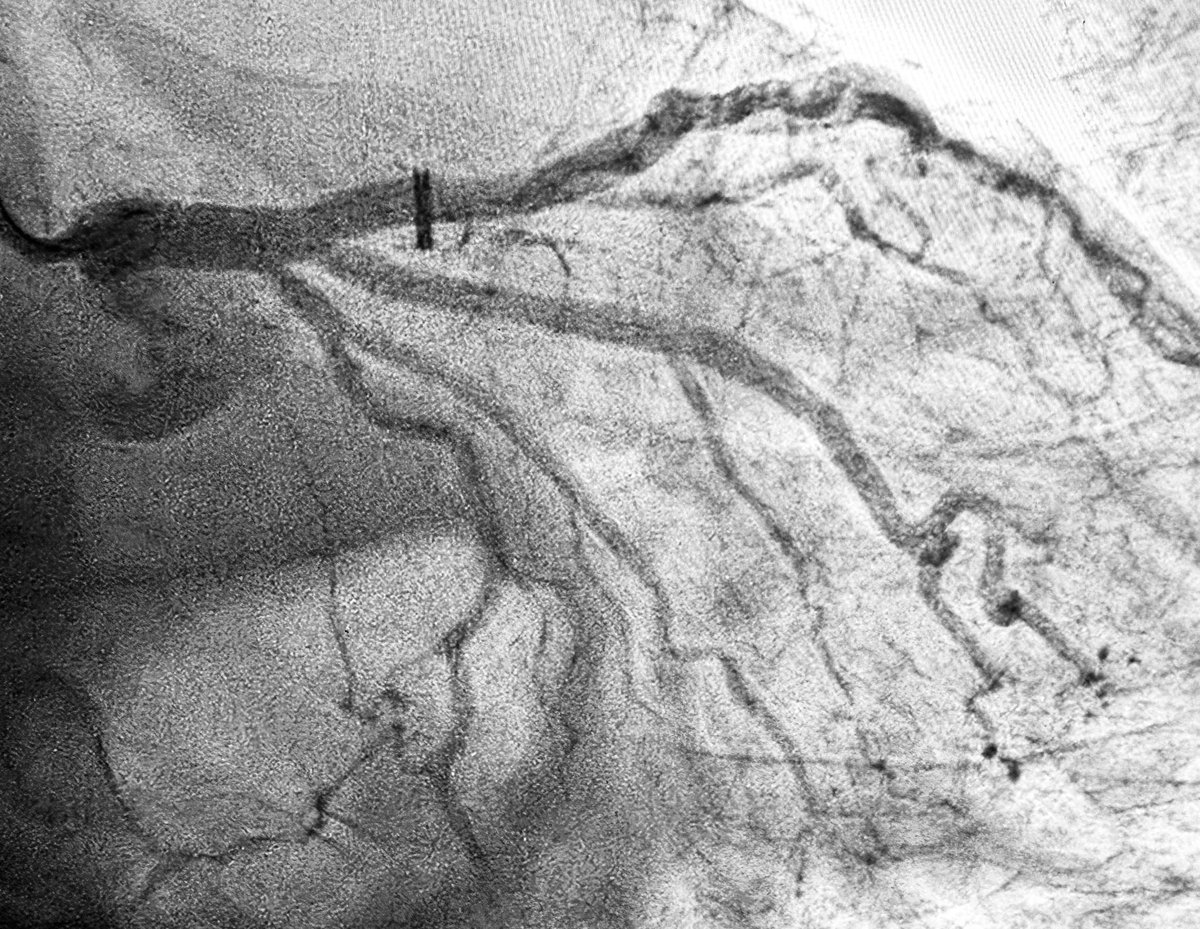

👍I’d say there is (at least) equipoise here (with IVI-guidance/optimization and dz not involving the trifurcation) re: #PCIvsCABG (LM Megatron DES: 5.3 mm distal to 6.0 mm ostial [with already-in-place IABP: removed post-PCI]): 🔗 jacc.org/doi/10.1016/j.……